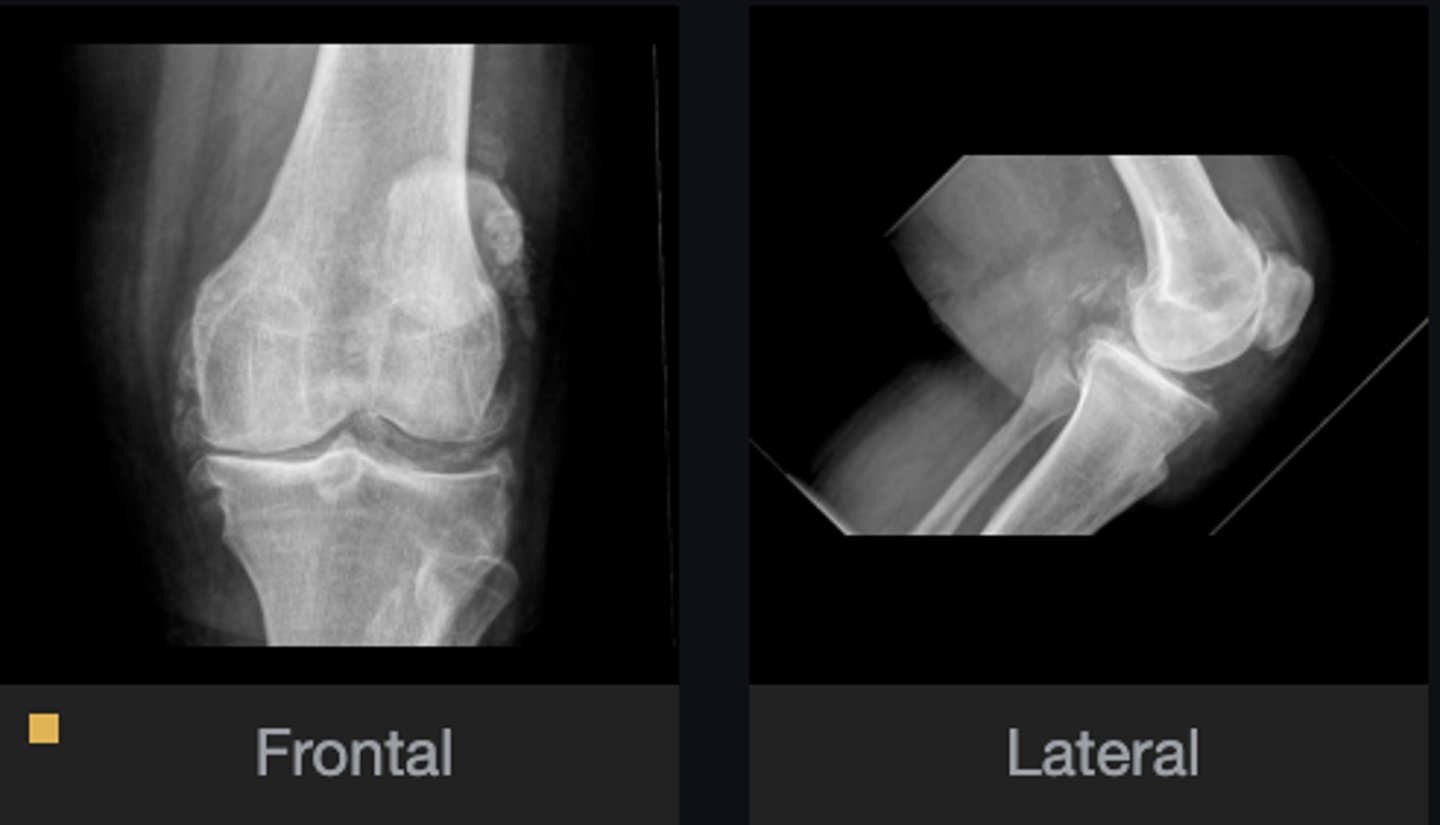

- Calcification of cartilage

- Meniscal calcification

- Non-uniform loss of joint space

- Osteophytes

- Subchondral cysts

- Subchondral sclerosis

- Subluxation

What abnormal findings are present?

CPPD

Most likely diagnosis?

- Knee

- Pubic symphysis

- Hand/wrist

- Hip

- Shoulder

- Elbow

- Spine

What are some areas that this disease likes to target?